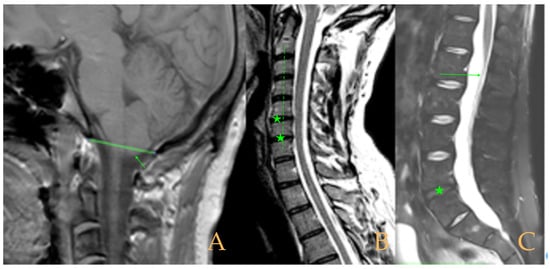

Magnetic resonance imaging showed a slight descent of the cerebellar tonsils, multiple diseased discs, and conus medullaris at the level of the middle third of the L1 vertebra. The X-ray images of the entire spine revealed a mild dextroconvex thoraco-lumbar scoliosis with 5° Cobb angle (Figure 1).

Figure 1. Imaging of patient 1. A: Mild descent of the cerebellar tonsils (arrows); B: multiple disc disease (arrows) and straightening of the cervical spine (interrupted line); C: conus medullaris at the middle third of L1 (arrow); and D: mild deviation of the vertebral column (interrupted lines).